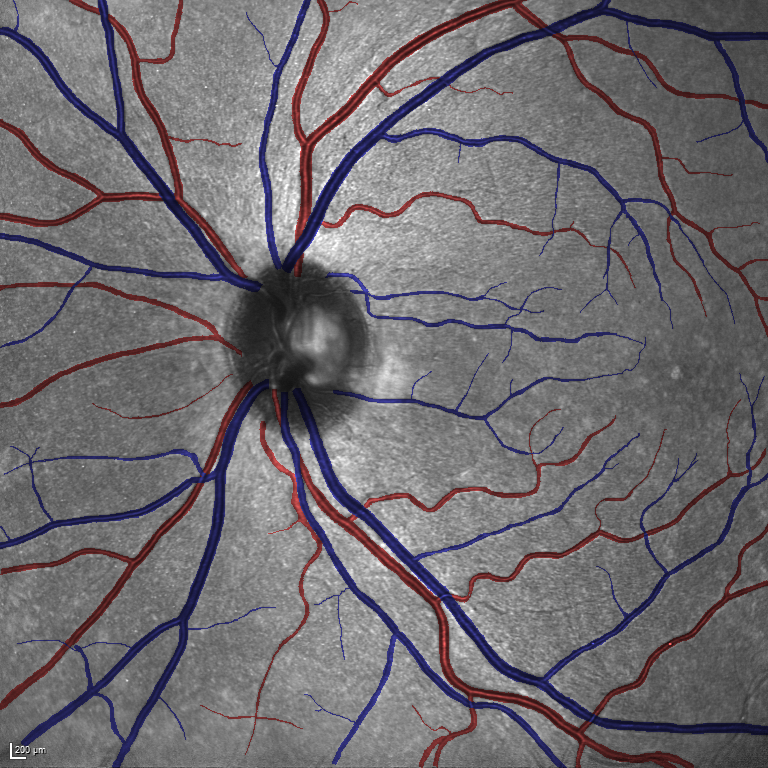

(a) Reference (b) Output (c) Width Map

As reported in Table IV, we compared the SegRAVIR model against competing deep learning-based segmentation approaches on the RAVIR dataset. Evidently, SegRAVIR outperforms these methods as judged by all metrics for artery and vein classes with a healthy margin. In terms of Dice score, SegRAVIR outperforms CE-NET, IterNet and AG-Net by , and for artery segmentation and by , and for vein segmentation, respectively. Fig. 4 presents a qualitative comparison of the semantic segmentation outputs of SegRAVIR, CE-Net, and U-Net. Specifically, SegRAVIR yields more accurate vessel topology (i.e., thickness and orientation) segmentation with higher pixel-wise classification accuracy.

(a) (b) (c)